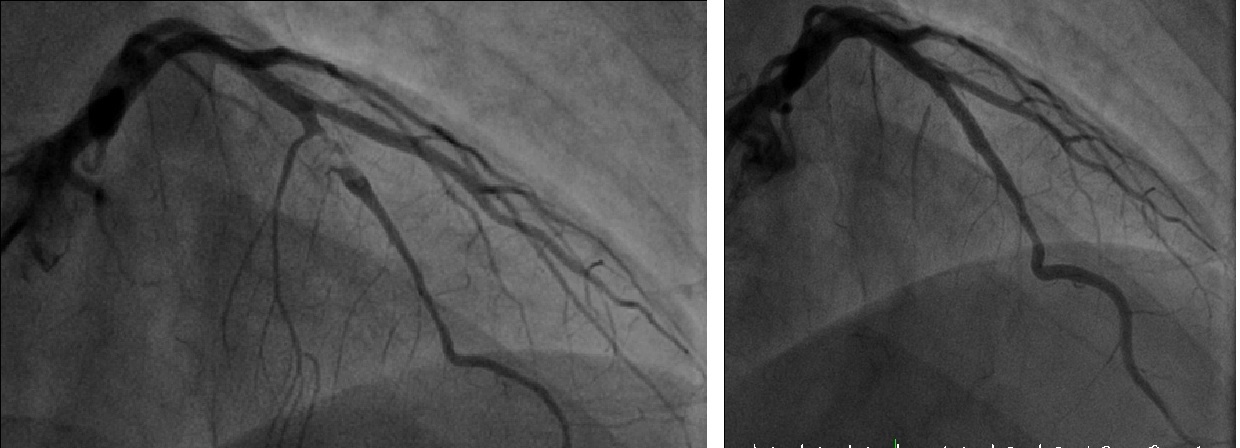

圖:患者心梗治療前(左)、後(右)對照。

因患者心功能不佳,血壓心跳又極不穩定,就由心臟外科吳清文主任先安排葉克膜裝設。隨即由內科部張建榮主任進行心導管檢查並在病患的左前降支冠狀動脈放置了擴張支架。幸運的是原本完全阻塞的冠狀動脈馬上就恢復血流,除了心臟肌肉開始正常收縮外,心臟頻率也立刻回復正常,葉克膜在輔助循環三天後,就順利拆除。轉住普通病房觀察5天後即返家休養。

內科部張建榮主任表示,急性心肌梗塞危險因子分為可改變和不可改變兩類,不可改變包括遺傳、年齡及性別,可改變的包括慢性疾病、飲食不當及吸菸。個案因左前降支冠狀動脈完全阻塞,所以出現了急性心肌梗塞猝死情形,為了打通阻塞的動脈就要進行心導管手術來進行氣球擴張並置放金屬支架,但評估患者術前的心肺狀況,先以葉克膜裝設才能避免更多風險產生。